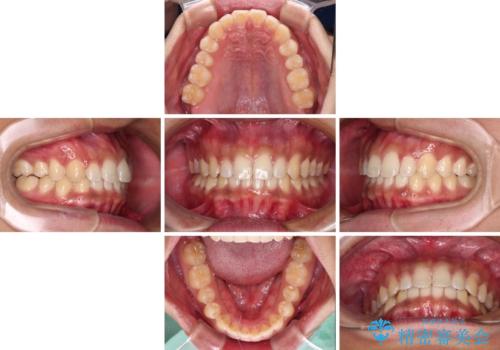

デコボコとディープバイトを治したい インビザラインによる矯正治療

- 前歯のデコボコや隙間と深い咬み合わせ(ディープバイト)を気にして来院された患者様です。

インビザラインによる上下歯列の側方拡大と後方移動、IPR(歯と歯の間を削る)にるスペースの獲得により、デコボコとディープバイトを改善することとしました。

気になっていたデコボコや隙間は改善し、きれいな歯列に整えることができました。

咬合力が非常に強い方であったため、これ以上のディープバイトの改善は困難となりました。